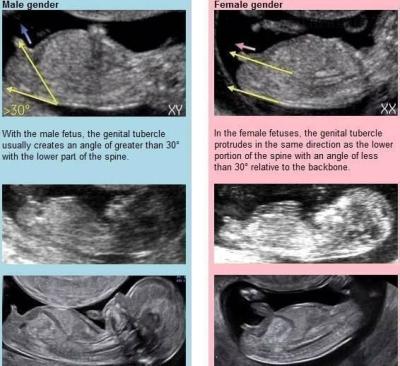

Dobrý den. Na ultrazvuku byl vidět ,, pindík, vrchem a stal🙈 Doktor řekl že tipuje kluka a za 3 tydny to pry bude vidět líp. Mam doma 4 holky🙈🤣 nepoznáte to Podle hrbolku nějakého? 🙈

Bude to krasne miminko…. Pahorek neni videt…